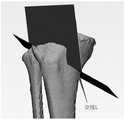

在本发明实施例中,如图3A所示,可以根据患者胫骨上的截骨位置,在三维图像中识别胫骨平台,即胫骨近端,外侧从最高点向下第一预设距离的第一关键点H,也可以称为轴点,其中第一关键点H的位置可以根据患者胫骨上截骨位置的不同而发生变化,例如,第一预设距离的取值范围大于或等于1.5cm,即第一关键点H可以位于胫骨平台外侧从最高点向下至少1.5cm处。本发明实施例对在胫骨平台的外侧识别第一关键点的实现方法不作限定。In the embodiment of the present invention, as shown in FIG. 3A, the tibial plateau, that is, the proximal end of the tibia, can be identified in the three-dimensional image according to the osteotomy position on the patient's tibia, and the outer side is the first predetermined distance from the highest point downward. The key point H may also be referred to as an axis point, wherein the position of the first key point H may vary according to the position of the osteotomy on the patient's tibia, for example, the value range of the first preset distance is greater than or equal to 1.5cm, That is, the first key point H may be located at least 1.5 cm downward from the highest point on the lateral side of the tibial plateau. The embodiment of the present invention does not limit the implementation method of identifying the first key point on the outer side of the tibial plateau.

202,在胫骨平台内侧从最高点向下第二预设距离处或者最凹处识别第二关键点。202. Identify a second key point on the inner side of the tibial plateau at a second preset distance or the most concave point downward from the highest point.

在本发明实施例中,如图3A所示,可以在三维图像中识别胫骨平台,即胫骨近端,内侧从最高点向下第二预设距离处或者最凹处的第二关键点A,也可以称为横向截骨点,例如,第二预设距离的取值范围为3cm~4cm,即第二关键点A可以位于胫骨平台内侧从最高点向下至少3cm~4cm处。本发明实施例对在胫骨平台的内侧识别第二关键点的实现方法不作限定。In the embodiment of the present invention, as shown in FIG. 3A , the tibial plateau, that is, the proximal tibia, the inner side of the tibia can be identified from the highest point downward at a second preset distance or the second key point A at the most concave position in the three-dimensional image, It can also be called a transverse osteotomy point. For example, the range of the second preset distance is 3cm~4cm, that is, the second key point A can be located at least 3cm~4cm downward from the highest point on the inner side of the tibial plateau. The embodiment of the present invention does not limit the implementation method of identifying the second key point on the inner side of the tibial plateau.

203,在胫骨平台距离外侧边缘第三预设距离处识别第三关键点。203. Identify a third key point at a third preset distance from the tibial plateau from the lateral edge.

在本发明实施例中,如图3B所示,可以在三维图像中识别胫骨平台,即胫骨近端,距离外侧边缘第三预设距离处的第三关键点D,例如,第三预设距离的取值范围为1cm~1.5cm,即第三关键点D可以位于胫骨平台上,与胫骨平台的外侧相距1cm~1.5cm处。本发明实施例对在胫骨平台上识别第三关键点的实现方法不作限定。In the embodiment of the present invention, as shown in FIG. 3B , the tibial plateau, that is, the proximal end of the tibia, can be identified in the three-dimensional image, and the third key point D at the third preset distance from the lateral edge, for example, the third preset distance The value range of D is 1cm~1.5cm, that is, the third key point D can be located on the tibial plateau, 1cm~1.5cm away from the outer side of the tibial plateau. The embodiments of the present invention do not limit the implementation method of identifying the third key point on the tibial plateau.

204,在胫骨平台中前部第四预设距离处识别第四关键点。204. Identify a fourth key point at a fourth preset distance from the middle-anterior portion of the tibial plateau.

在本发明实施例中,如图3C所示,可以在三维图像中识别胫骨平台,即胫骨近端,中前部第四预设距离处的第四关键点M和N,例如,第四预设距离的取值范围为1.5cm~2cm,即第四关键点M和N可以选取胫骨平台上中前部1.5cm~2cm处的两个点,并使这两个点的连线MN与胫骨冠状面平行。本发明实施例对在胫骨平台上识别第四关键点的实现方法不作限定。In the embodiment of the present invention, as shown in FIG. 3C , the tibial plateau, that is, the proximal end of the tibia, the fourth key points M and N at the fourth preset distance in the front part of the tibia can be identified in the three-dimensional image, for example, the fourth preset distance The value range of the distance is 1.5cm~2cm, that is, the fourth key points M and N can be selected from two points at 1.5cm~2cm in the middle and anterior part of the tibial plateau, and make the connection line MN between these two points and the tibia. The coronal planes are parallel. The embodiments of the present invention do not limit the implementation method of identifying the fourth key point on the tibial plateau.

在本发明实施例中,如图3B所示,在三维图像中识别出胫骨平台上,即胫骨近端,距离外侧边缘第三预设距离处的第三关键点D之后,可以通过第三关键点D做胫骨矢状面的第一平行面G,本发明实施例对通过第三关键点确定第一平行面的实现方法不作限定。In this embodiment of the present invention, as shown in FIG. 3B , after identifying the third key point D on the tibial plateau, that is, the proximal end of the tibia, at a third preset distance from the lateral edge in the three-dimensional image, the third key Point D is the first parallel plane G of the sagittal plane of the tibia, and the embodiment of the present invention does not limit the implementation method of determining the first parallel plane through the third key point.

在本发明实施例中,如图3C所示,在三维图像中识别出胫骨平台上,即胫骨近端,中前部第四预设距离处的第四关键点M和N之后,可以通过第四关键点M和N做胫骨冠状面的第二平行面F,例如,通过连线MN生成胫骨冠状面的第二平行面F ,本发明实施例对通过第四关键点确定第二平行面的实现方法不作限定。In the embodiment of the present invention, as shown in FIG. 3C, after identifying the fourth key points M and N at the fourth preset distance on the tibial plateau, that is, the proximal end of the tibia, in the front part of the tibia in the three-dimensional image, the The four key points M and N are used as the second parallel plane F of the coronal tibia. For example, the second parallel plane F of the coronal tibia is generated by connecting line MN. The implementation method is not limited.

在本发明实施例中,如图3D所示,可以在三维图像中通过第一关键点H和第二关键点A做胫骨冠状面的第一垂面P,使第一截骨面P沿第一垂面E从胫骨内侧截开胫骨,并截止于第一平行面G和第二平行面F,例如,可以通过第一关键点H和第二关键点A的连线HA做胫骨冠状面的第一垂面E,第一垂面E为与胫骨平台保持一定倾斜角度的平面,第一截骨面P沿第一垂面E从胫骨内侧截开胫骨,截透胫骨后侧,不截透胫骨外侧和前侧,截骨深度至第一平行面G和第二平行面F为止。In the embodiment of the present invention, as shown in FIG. 3D, the first vertical plane P of the coronal plane of the tibia can be made through the first key point H and the second key point A in the three-dimensional image, so that the first osteotomy plane P is along the first vertical plane of the tibia. A vertical plane E cuts the tibia from the medial side of the tibia, and ends at the first parallel plane G and the second parallel plane F. For example, the coronal plane of the tibia can be drawn through the connecting line HA between the first key point H and the second key point A. The first vertical plane E, the first vertical plane E is a plane that maintains a certain inclination angle with the tibial plateau, and the first osteotomy plane P cuts the tibia from the inner side of the tibia along the first vertical plane E, cuts through the posterior side of the tibia, and does not cut through the tibia. On the lateral and anterior sides of the tibia, the osteotomy depth reaches the first parallel plane G and the second parallel plane F.

在本发明实施例中,如图3E所示,可以在三维图像中通过第一垂面E与第二平行面F的交线L,在与第一垂面E呈110-130°角做第二截骨面Q,使第二截骨面Q截透胫骨前方的内外侧,并截止于第一截骨面P,例如,可以通过第一垂面E与第二平行面F的交线L,在与第一垂面呈110-130°角的方向上做第二截骨面Q,使第二截骨面Q横向截透胫骨前方的内外侧,纵向截骨深度至第一截骨面P为止。其中,第一截骨面P与第二截骨面Q均为平面,In the embodiment of the present invention, as shown in FIG. 3E , in the three-dimensional image, the intersection line L between the first vertical plane E and the second parallel plane F can be used to make the first vertical plane E at an angle of 110-130°. Two osteotomy planes Q, so that the second osteotomy plane Q cuts through the inner and outer sides of the front of the tibia, and ends at the first osteotomy plane P, for example, it can pass through the intersection L of the first vertical plane E and the second parallel plane F , make the second osteotomy surface Q in the direction of 110-130° angle with the first vertical plane, so that the second osteotomy surface Q transversely cuts through the inner and outer sides of the front of the tibia, and the longitudinal osteotomy depth reaches the first osteotomy surface up to P. Among them, the first osteotomy surface P and the second osteotomy surface Q are both planes,